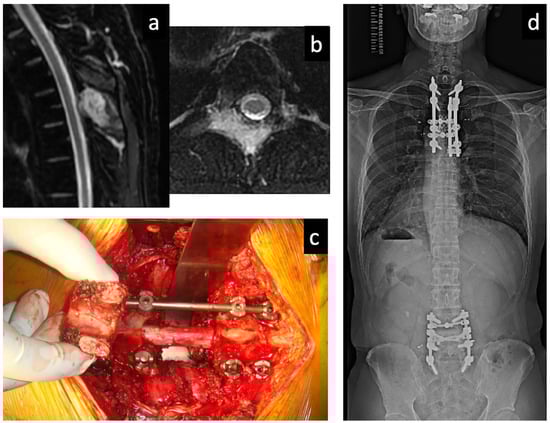

- Demura, S.; Kawahara, N.; Murakami, H.; Abdel-Wanis, M.E.; Kato, S.; Yoshioka, K.; Tomita, K.; Tsuchiya, H. Total en bloc spondylectomy for spinal metastasis in thyroid carcinoma. J. Neurosurg. Spine 2011, 14, 172–176. [Google Scholar] [CrossRef]

- Kato, S.; Murakami, H.; Demura, S.; Fujimaki, Y.; Yoshioka, K.; Yokogawa, N.; Tsuchiya, H. The impact of complete surgical resection of spinal metastases on the survival of patients with thyroid cancer. Cancer Med. 2016, 5, 2343–2349. [Google Scholar] [CrossRef] [Green Version]

- Kato, S.; Murakami, H.; Demura, S.; Yoshioka, K.; Yokogawa, N.; Yonezawa, N.; Shimizu, T.; Oku, N.; Kitagawa, R.; Tsuchiya, H. Kidney and Thyroid Cancer-Specific Treatment Algorithm for Spinal Metastases: A Validation Study. World Neurosurg. 2019, 122, e1305–e1311. [Google Scholar] [CrossRef] [PubMed]